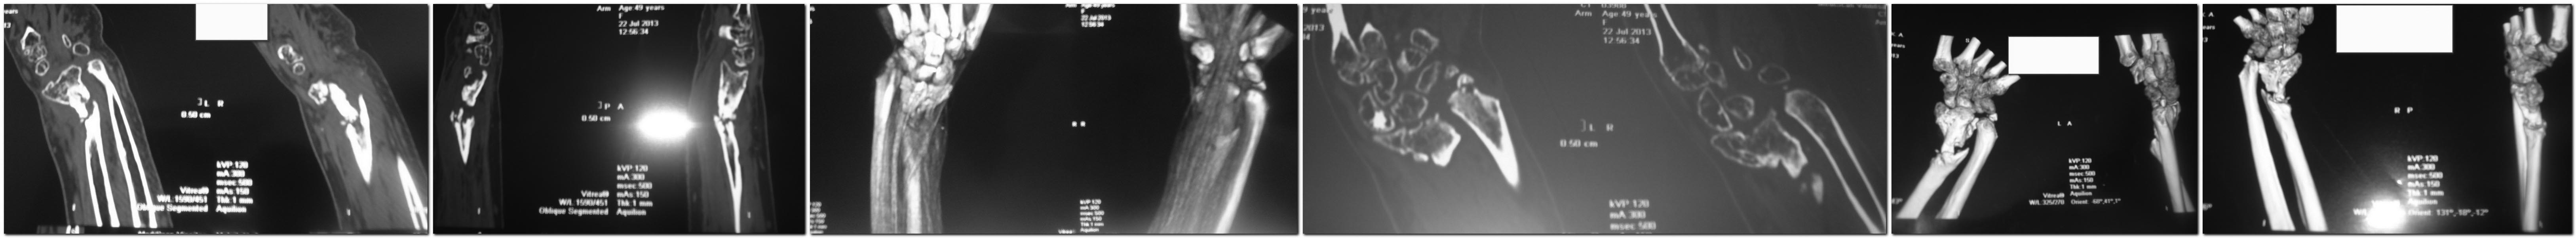

Здравствуйте уважаемые коллеги, просим Ваше мнение по поводу лечения ложного сустава дистальной части лучевой кости после костной пластики и остеомиелита Женщина 55 лет, травма 8 мес назад, был открытый перелом дистального метаепифиза правой лучевой кости А2, осложненный флегмоной предплечья через неделю после травмы. К нам обратилась через 1 мес после травмы, с иммобилизацией перелома в АВФ (снимок 1) и свищом с гнойными выделениями. Нами произведена резекция кости в пределах здоровых тканей ( около 3 см) проксимально 8 см на фоне здоровой трубчатой кости в канале густой эксудат темного цвета, который эвакуирован и все промыто антисептиками ( снимок 2). Установлены бусы с антибиотиком. Рана полностью зажила через 1.5 мес, бусы удалены.3 месяца выждали, на фоне отсутствия воспаления выполнили костную пластику из крыла подвздошной кости, АВФ 2.5 мес (снимок 3), + гипс 1 мес. На сегодняшний день отмечается лучевая косорукость, пат подвижность в месте ложного сустава, отсутствие воспаления.План: костная пластика + LCP из переднего доступа, укорочение локтевой кости или удаление головки локтевой кости. Уважаемые коллеги, поделитесь пожалуйста мнением по тактике дальнейшего лечения пациентки. С уважением , Александр.

К Вашему вниманию СКТ